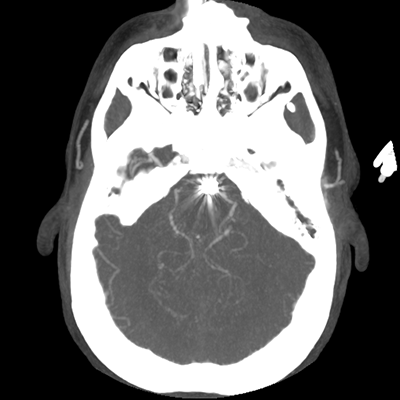

The patient goes down to CT. The following images are obtained. The subdural fluid collection is stable, as is the ventricular caliber.

Starting with the non-contrast head CT, we can appreciate that there's actually not much residual subarachnoid blood at all; it's essentially all resorbed already (and cleared through the EVD). The ventricular caliber is stable. With the CTA head (for convenience's sake, the MIPs were shown), it's subtle, but we can see that the PCAs on each side are not as smooth and regular. The right MCA, starting at the bifurcation, also becomes narrower. This is [radiographic] vasospasm. Now, looking at the CT perfusion-- specifically, the Tmax (MTT) map that were selected-- there's clearly some abnormality within the bilateral cerebellar hemispheres and occipital lobes. Not a lot, but it's there. Delving further into this map, we can appreciate that the areas of abnormality are mainly green, signifying that these areas have Tmax > 6 seconds. This is the threshold that is specific, not sensitive, for vasospasm.

Putting this all together, we have thus identified radiographic vasospasm with the vessel imaging, with perfusion abnormalities that are concordant with it. Does the area of vasospasm and hypoperfusion correlate with the patient's clinical exam?

Yes! It does. The patient had a decline in level of consciousness with diffuse loss of motor function. This does correlate to the basilar territory. (Alternatively, bilateral MCA vasospasm could also be responsible, reminding us that a decline in consciousness could technically be focal/multifocal.) Thus, we can say that this patient does have clinical vasospasm. Whether this will develop into irreversible DCI remains to be seen; at least, the non-contrast head CT and the other portions of the CT perfusion (not shown) currently don't [yet] suggest infarction.